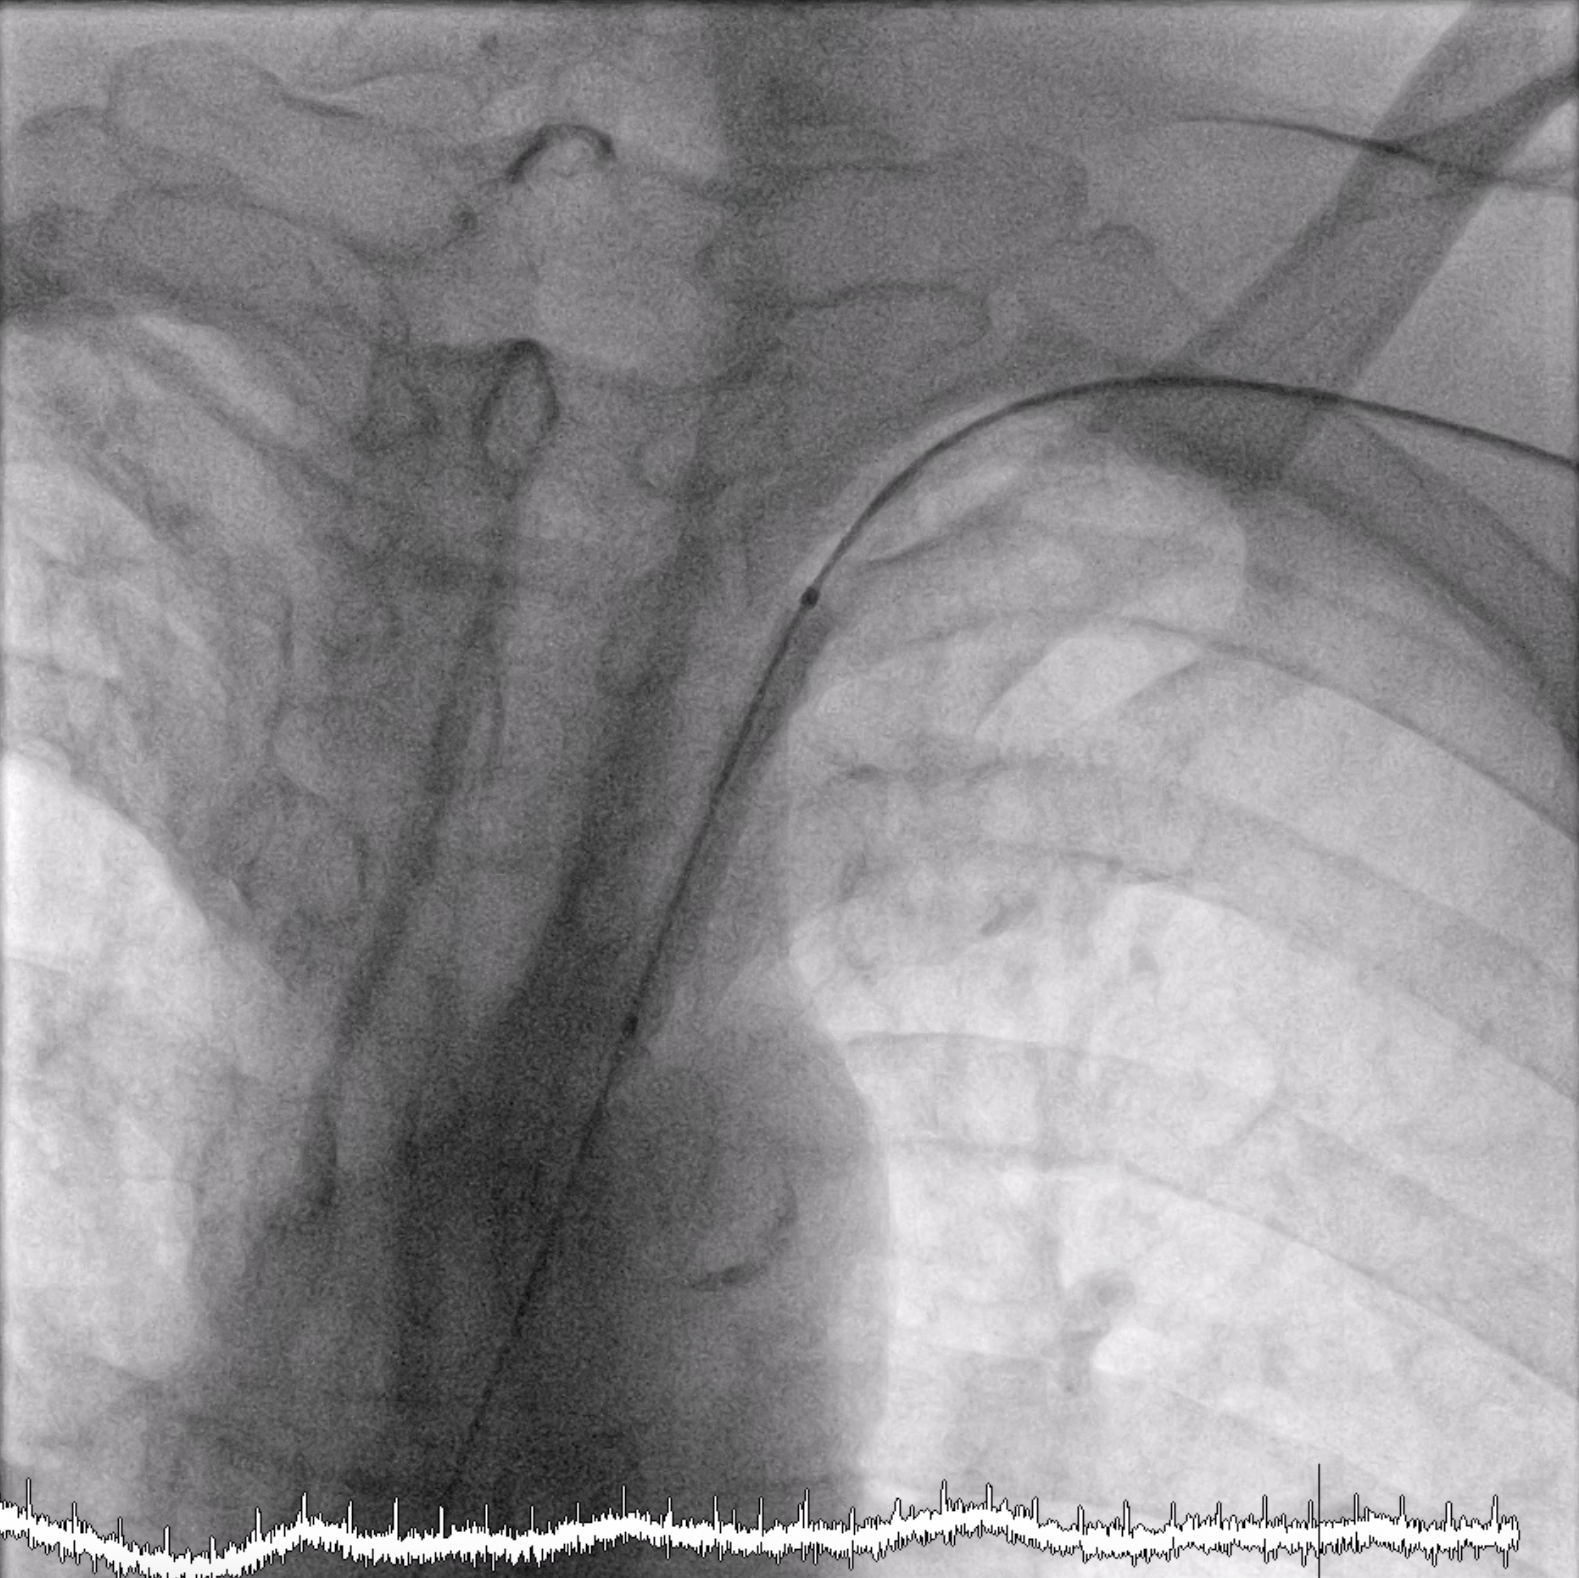

After we performed cine-angiography of the left subclavian artery using AP view, we drew the upper and lower border of the stenosis location with permanent marker on the machine¡¯s screen. We decided not to use a guiding catheter to intervene the left subclavian stenosis. Using JR 4.0 diagnostic catheter, we inserted 0.035¡± PTFE J tip guide wire 150 cm into the left subclavian artery, crossed the lesion, and secured distally into the aorta.We pulled out the JR 4.0 diagnostic catheter, then we delivered a MustangTM Balloon Dilatation Catheter (Boston Scientific) 5.0 x 40 mm into the lesion. We positioned the Mustang balloon according to the ¡®mark¡¯ that we made in the screen, then inflated it.After pre-dilating with the balloon, next we delivered ExpressTM Vascular LD Stent (Boston Scientific) 8.0 x 27 mm into the lesion (according to the ¡®mark¡¯) and deployed the stent. After that, we advanced the balloon stent about 3-4 mm further and post-dilated the stent.The final result was good with no residual stenosis and no dissection.